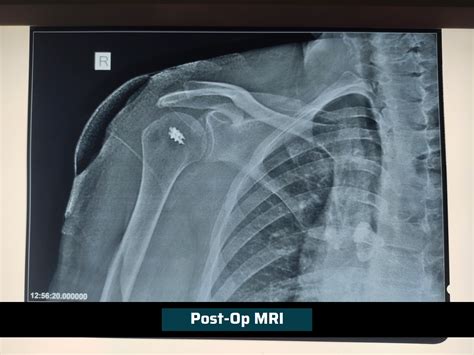

• Undergo necessary diagnostic tests, such as X-rays or MRI scans, to assess the extent of the injury.